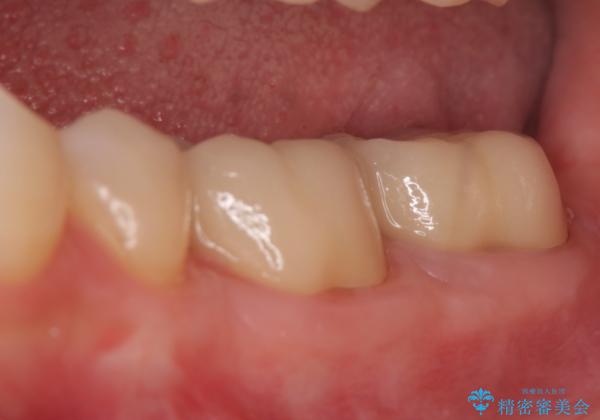

歯周外科手術終了後、歯茎の回復を待ち左下6、7ともにオールセラミッククラウン(スタンダード)による補綴を行いました。

今回用いたオールセラミッククラウンはジルコニアフレームという白い素材の上にセラミックを盛っているため、審美性が非常に高いのが特徴です。

また、ジルコニアは人工ダイヤモンドの材料にも使われているほど高い強度を持っており、そのためオールセラミッククラウンは審美性だけでなく、奥歯やブリッジの補綴も可能とするクラウンです。